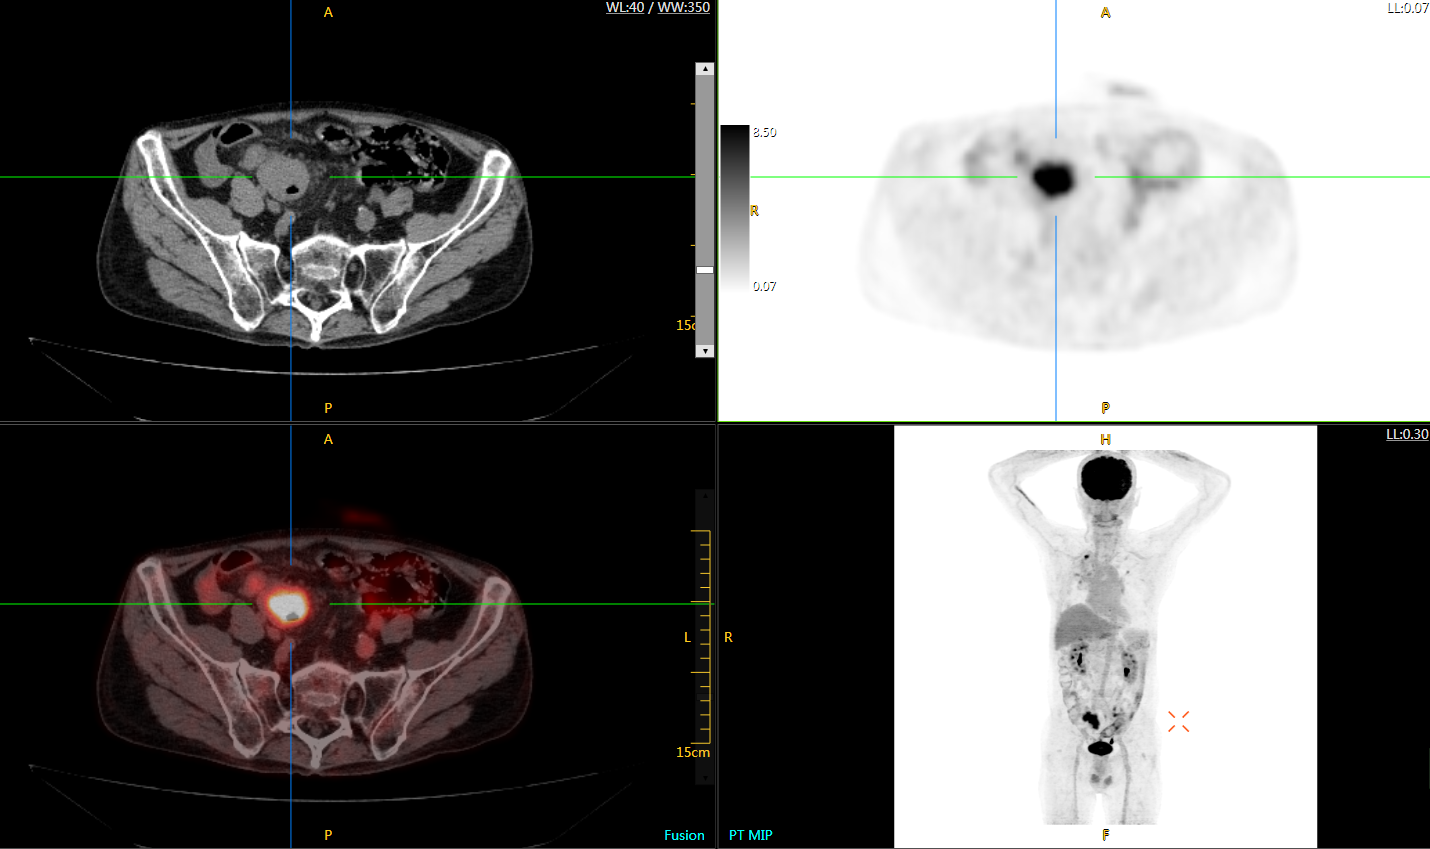

uExplorer探索者不再局限于傳統(tǒng)靜態(tài)代謝過程3D成像,而是在此基礎(chǔ)上新增一個維度——時(shí)間,從而實(shí)現(xiàn)4D全景成像。

注射總劑量為7.8mCi,14分鐘全身采集時(shí)間,在擁有超高靈敏度與超高分辨率的uEXPLORER上,即可得到展示顯示人體諸多精細(xì)結(jié)構(gòu)的高清三維圖像。

注射總劑量為7.8mCi,注射后1.6小時(shí),基于uEXPLORER探索者掃描1分鐘的圖像

注射總劑量為0.67 mCi FDG(低于常規(guī)劑量的十分之一),基于uEXPLORER探索者掃描15分鐘的圖像

注射總劑量為6.9mCi,注射后10小時(shí),基于uEXPLORER探索者掃描14分鐘的圖像